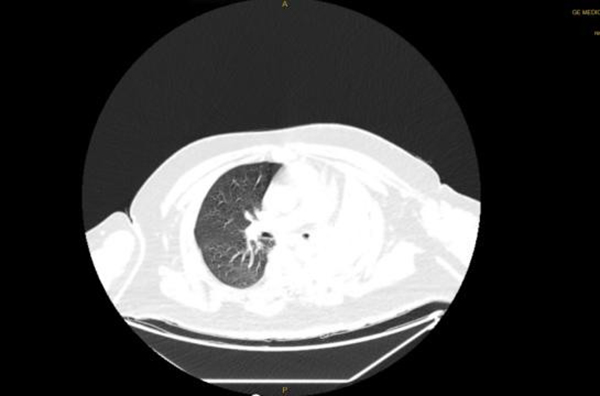

4月14日,王先生因“憋喘伴發(fā)熱咳嗽半月余”到徐州醫(yī)科大學(xué)附屬醫(yī)院急診就診。據(jù)王先生家人介紹,患者半個(gè)多月來,憋喘不斷加重,先后在徐州市多家醫(yī)院就診,考慮左肺不張伴感染,但通過積極抗感染治療,憋喘無改善并逐漸加重,同時(shí)出現(xiàn)發(fā)熱癥狀,體溫最高近39攝氏度。徐醫(yī)附院呼吸與危重癥醫(yī)學(xué)科何軍主任會(huì)診后,考慮患者智力異常,進(jìn)食方式特殊,不排除誤吸的情況,閱片后發(fā)現(xiàn)左主支氣管內(nèi)存在異物可能,需行氣管鏡檢查進(jìn)一步明確肺內(nèi)情況。考慮患者一般情況差,存在I型呼吸衰竭,肺部感染重等情況,于是將其收治在呼吸重癥監(jiān)護(hù)室(RICU)。

患者入院后進(jìn)行高流量氧療和抗感染治療,因?yàn)槠浞逝趾喜⒑粑ソ,肺部感染重,氣管鏡風(fēng)險(xiǎn)高,在與家屬充分溝通后,呼吸ICU團(tuán)隊(duì)于4月15日為王先生行床旁氣管鏡檢查,鏡下發(fā)現(xiàn)左主支氣管內(nèi)一白色圓形異物,表面為壞死覆蓋,清除壞死組織后,異物質(zhì)硬,表面光滑,無法鉗取。同時(shí)患者病情危重、麻醉評(píng)估風(fēng)險(xiǎn)極高,在陳碧主任的主持下,呼吸ICU團(tuán)隊(duì)經(jīng)過討論后決定行床旁氣管鏡取異物術(shù)。

后續(xù)給與積極抗感染等治療,復(fù)查胸片示左肺不張改善,體溫正常,炎癥指標(biāo)下降,再次復(fù)查氣管鏡下可見痰量較前明顯減少,總體病情好轉(zhuǎn),4月23日轉(zhuǎn)到普通病房繼續(xù)治療;颊呒覍俦硎荆氜D(zhuǎn)三家醫(yī)院就醫(yī),還是徐醫(yī)附院最值得信任,對(duì)呼吸ICU全體醫(yī)護(hù)人員表達(dá)了敬意和衷心感謝。